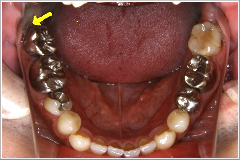

これは横向きに出てきた親知らずとその前の歯との間に食べ物が詰まり、取れなくなった為に奥の方まで炎症が広がり、結果的に前の歯を抜かなければならなくなった症例です。 この患者さんは「右下奥歯が動き出し、痛くて噛めなくなりました」といって来院されました。

ところが実際には、むし歯は前歯よりも奥歯の方がひどかったのです。歯を磨く事を止めてしまった結果がここに出てしまったのです。

その写真をここに載せますので見て下さい。

親知らずは虫歯にならず、その前の歯だけに大きな虫歯を造っている親知らずもあります。

また、一見それほど大きな虫歯ではない様に見える歯でも、少し顔を出した親知らずの為に抜かなければならぬ程の大きな虫歯になっている事もあるのです。